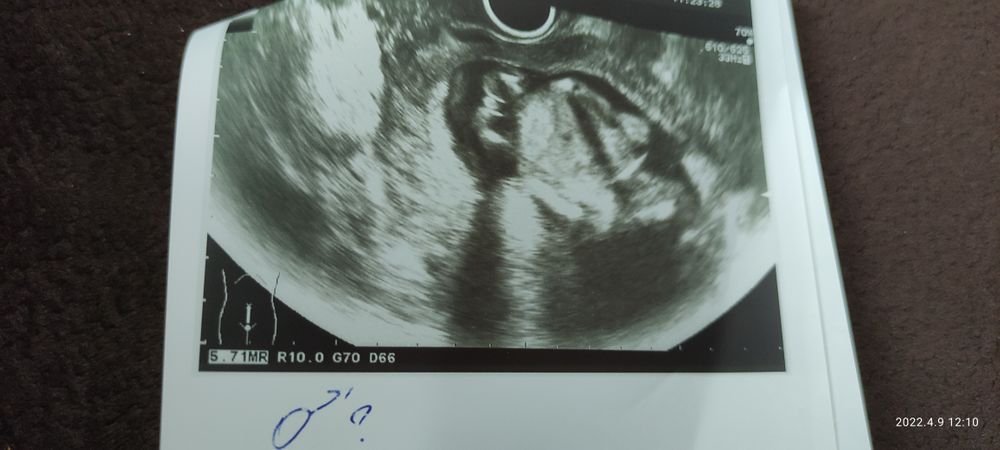

Самое интересное, что потом совсем угадайка началась. Так обычно ведут себя девочки, мальчики обычно ничего не скрывают,девочки больше крутятся, а мальчики нет, в общем кошмар😞 Буду ждать 2скрининг

Допплер Третья дочка)